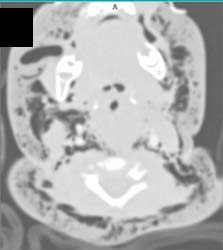

Aortic Aneurysm With Ulceration